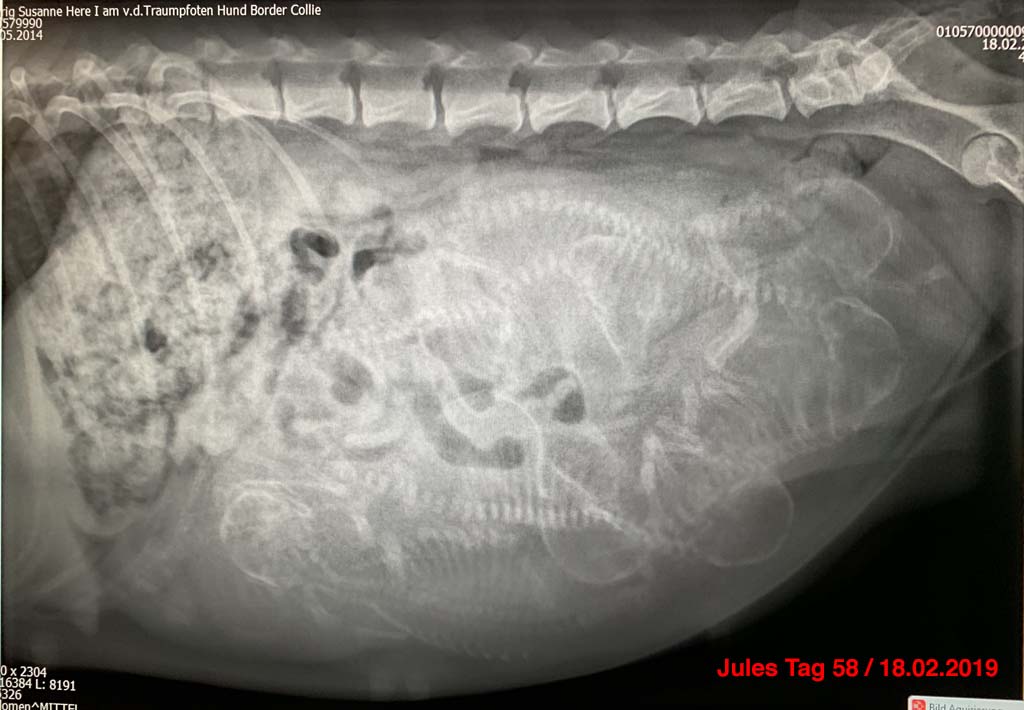

Heute haben wir bereits Tag 58 der Trächtigkeit von Jules. Jules hat deutlich an Gewicht zugelegt und sucht viel unsere Nähe. Das Röntgenbild von heute hat eindeutig bestätigt, dass es nicht das leckere Futter der letzten Tage war, welches den Zeiger auf der Waage so kräftig nach oben bewegt hat. Wir hoffen nun in den kommenden Tagen auf eine problemlose Geburt unseres R-Wurfs. Wir halten euch alle wie gewohnt auf dem Laufenden, wenn es wieder wichtige Neuigkeiten gibt.

Röntgen an Tag 58 der Trächtigkeit